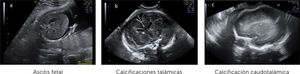

Ingresa a las 28+2 semanas, por alteraciones cerebrales del feto en ultrasonido de rutina, sugerentes de infección por citomegalovirus (CMV) (hiperecogenicidad periventricular, adhesiones intraventriculares y quiste subependimario temporal) (Figura 1 a-c). Al ingreso resulta PCR positiva para CMV por amniocentesis realizada a las 27 semanas y negativa en sangre materna.

El diagnóstico por ultrasonido no es fácil, depende de factores como el hábito materno, posición fetal, localización placentaria, requiere entrenamiento y no es específico, ya que muchos agentes etiológicos dan hallazgos similares. Su sensibilidad es de alrededor de 80–85% 21, pero aumenta a un 95% al combinar con RM y sobre todo cuando el diagnóstico de infección ya está verificado22, reforzando el concepto que ambas son técnicas complementarias, que además tienen un alto valor predictivo negativo para compromiso fetal grave23. En general las alteraciones imagenológicas se suelen ver unas 12 semanas después de la infección materna y, en ausencia de hallazgos, si bien, no se descarta lesiones auditivas, si se sabe que hay buen pronóstico neurológico fetal. (Figura 2 a-c).